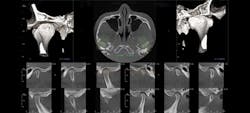

13x15 covers the entire maxillofacial region.

Larger fields of view offer broader diagnostic capabilities, including airways.